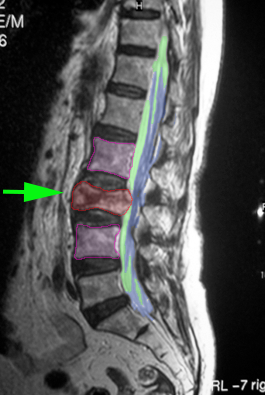

Κάταγμα Ο1 σπονδύλου (κόκκινο) με παραμόρφωση του σχήματός του. |